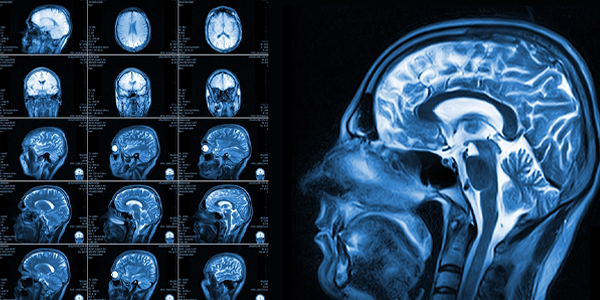

• Manyetik rezonans görüntüleme (MR): MR, BT'den daha detaylı görüntüler sağlar ve kanamanın nedenini belirlemeye yardımcı olabilir.

Beyin_MR_4f7394c6.webp